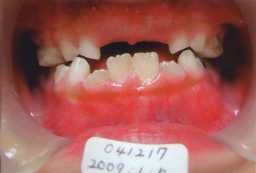

私の娘:掛園 綾です。2002年01月19日生 2007年03月19日(5才2ヶ月) 骨格性反対咬合(C〜C) 矯正用の床装置を作っても寝ると すぐ自然に吐き出す。また床装置を入れると 寝れないと主張。 |